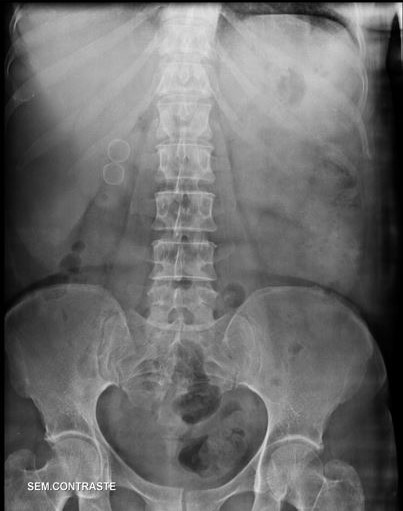

Q

DOR LOMBAR, AP DA COLUNA LOMBAR, PEGANDO TODO ABDOME.

ACHADOS RADIOLÓGICOS? DIAGNÓSTICO?

A

HÁ IMAGENS CÁLCICAS ( SETAS AMARELAS )NA REGIÃO EPIGÁSTRICA EM PROJEÇÃO DO PÂNCREAS ( NIVEL DE L1 E L2)

PANCREATITE CRÔNICA

HÁ GASES, FEZES E RESÍDUOS MEDICAMENTOSOS (COMPRIMIDOS) NO CÓLON.